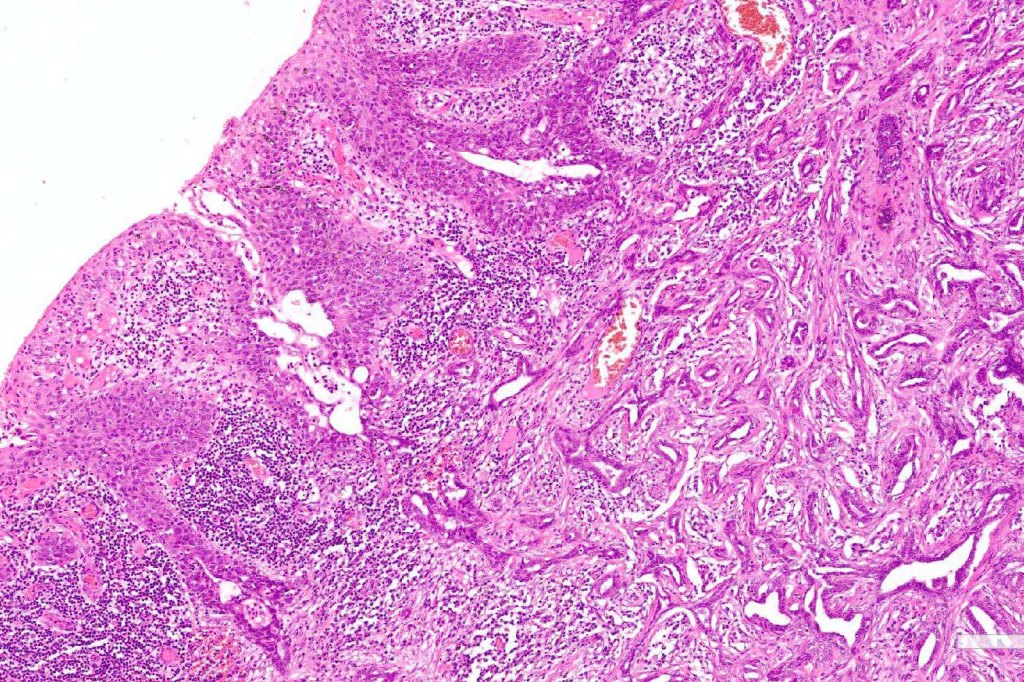

•Ulceration and solar elastosis are common

•Widely infiltrating biphasic tumor

•Superficial SCC

•Adenocarcinoma in deeper reaches

•Deep part may show both ducts and glands

•Often extends to the subcutaneous fat